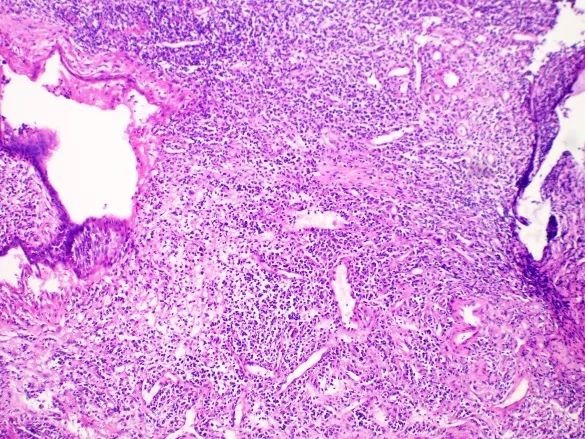

病理所示

结合病史,符合鼻咽癌转移(图 6-7 )。

图 6 鼻咽癌肝转移镜下表现